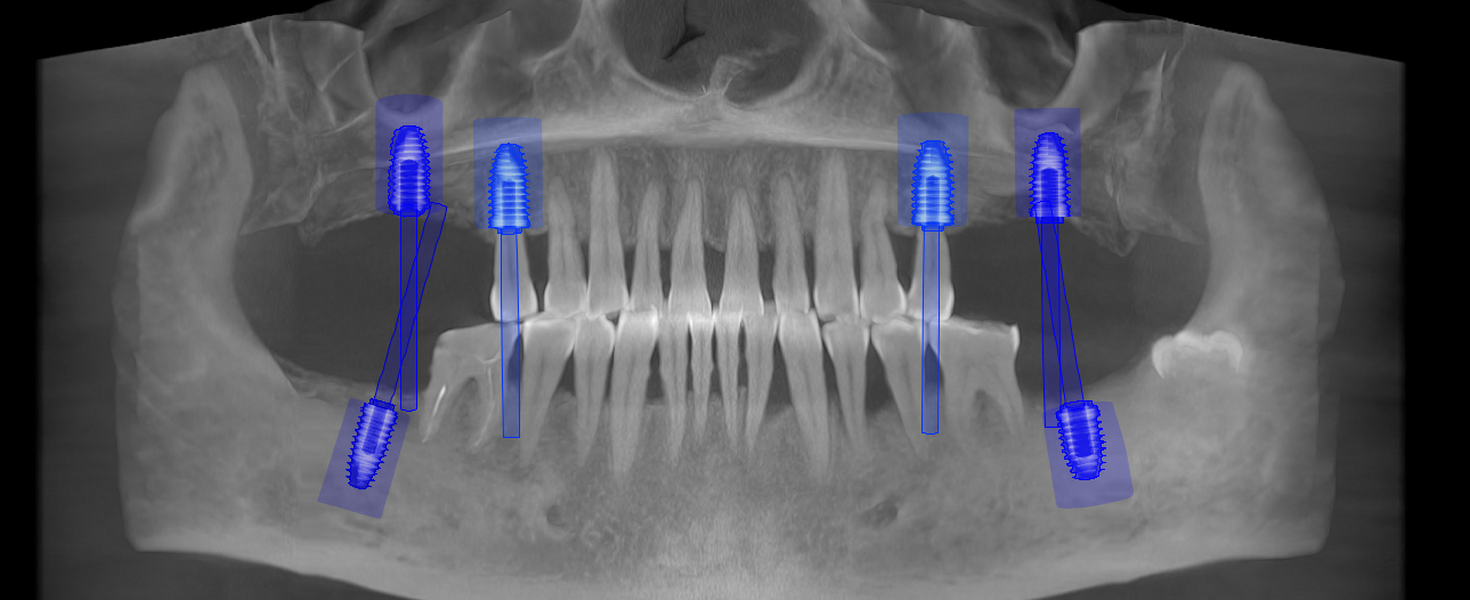

- Punte pe implanturi dentare – fixată pe 2 sau mai multe implanturi

- Șlefuirea dinților de susținere sau inserarea implanturilor

- Tehnologie CAD/CAM și scanare digitală 3D